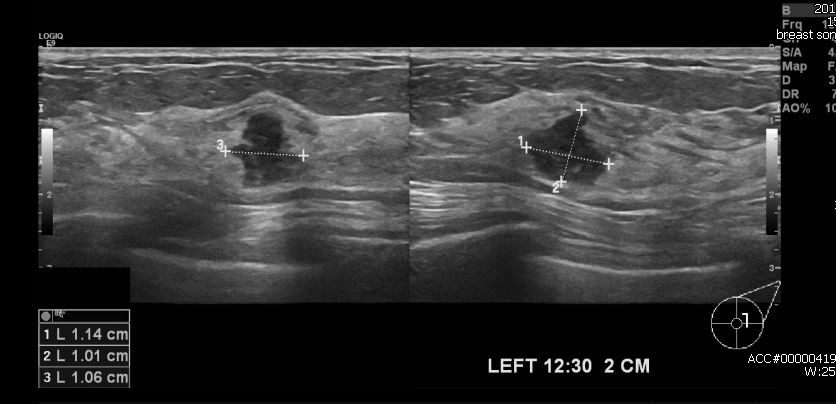

건겅검진상 이상 소견으로 내원하신 40대 여성분으로 본원 초음파 시행 후

좌측 유방의 12시 30분 방향에서 2cm 떨어진 거리의 혹 조직검사 시행하여

좌측 침윤성 유관암 진단 되었습니다.